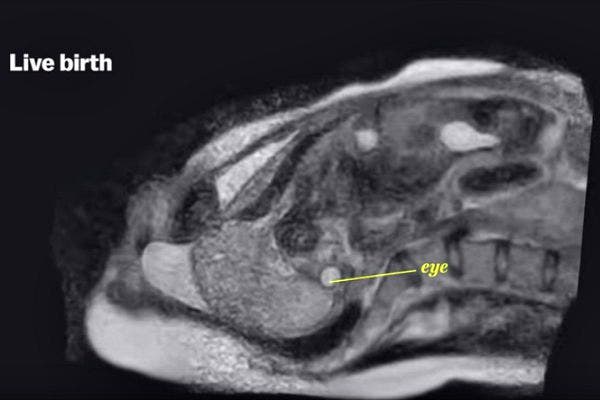

6. Nine months later and out comes a baby.

All photos: YouTube

Since MRI machines are very loud, they stopped the video of the live birth when the baby's head emerged, since they didn't want the noise to damage the baby's hearing.